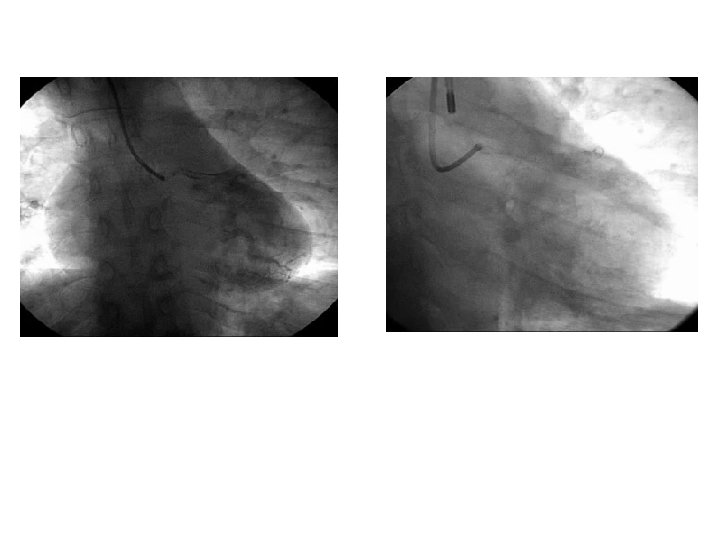

After PTCA • • • Dobutamine 10 mic IAPB BP 90 Pic troponin: 42 Stable biologie Clinical signs of poor peripheral perfusion after few hours ECMO

No recovery after 10 days

HMII Implantation instead of high emergency list cardiac transplantation ØTo test for potential recovery ØTo buy time before transplantation

After implantation • Good general status recovery • Discharged directly to home after 20 days • Echocardiography: – Good LV unloading – No aortic valve opening – Myocardial contraction slightly better

Explantation: September

> 5 years • Doing well on ACE inhinbitor and beta bloquers • Normal life • Back to physical activies • Disappearance of apical clot • Isotopic EF: 60%